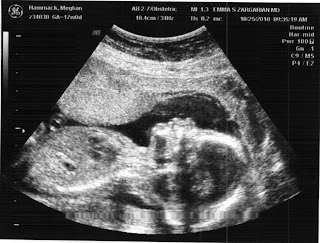

Here are the ultra sound pics from our appointment today. Everything went very well. The heartbeat was strong and the brain looked clear of cysts and other abnormalities which was a huge relief after Ben's scare with the choroid plexus cyst. It was so wonderful to see the baby, and finally made it feel very real! We are trying to come up with a nickname for the baby to reference to Ben and others and have come up empty handed. We have Skeletore but thought that might be slightly inappropriate, well at least I felt that way:) Any ideas would be greatly appreciated!!!